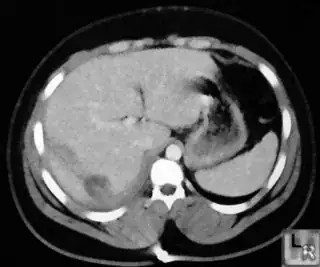

Below I apply two successive morphological openings to the image using a 3x3 circular kernel, and then apply k-means clustering to the gray levels. From your sample images and some I found on the internet, I decided to set k = 4. If you are using high-resolution images, first downsample them to dimensions ~400-600. Otherwise the morphological operation may not have a significant effect, and the k-means will be slow.

Below are some of the opened and segmented images. Of course there's more to be done in terms of

- separating out the liver region

- generalizing this to a large dataset

but hope this is at least a starting point.

Update

You might be able to narrow down the region or interest by filtering out the darkest and the lightest regions from the segmented image. For this, use the k-means cluster centers, check for the extreme values (max and min) and remove the corresponding k values from the labeled image. Then you can look for large structures to the left of the result image. Worst case, you might get a hole on the left side when the extreme region filtering goes wrong. I've updated the code and results.